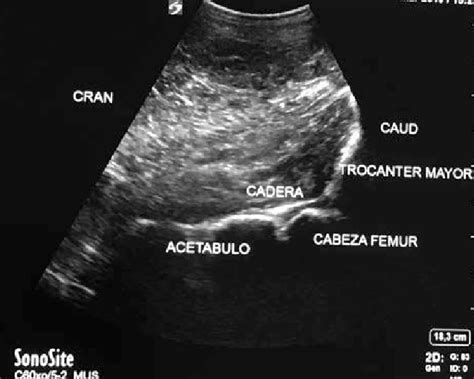

Las piernas

Se visualiza el fémur, el hueso más largo y fuerte del cuerpo. También se pueden observar la tibia y el peroné en la parte inferior de la pierna, así como la rodilla y el tobillo.